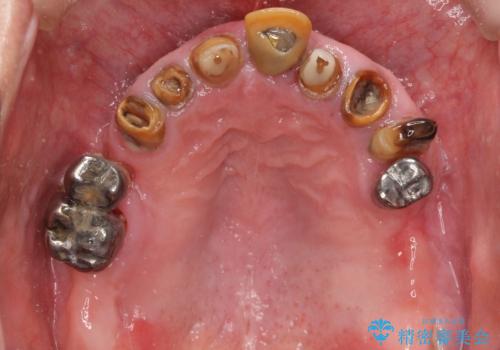

- 前歯の被せ物がとれたまま放置されていた患者様です。

前歯4本のうち3本の被せ物が脱離し、残りの1本の被せ物は劣化し変色していました。

古い被せ物や土台・虫歯をしっかり除去したのち、セラミック治療を行いました。